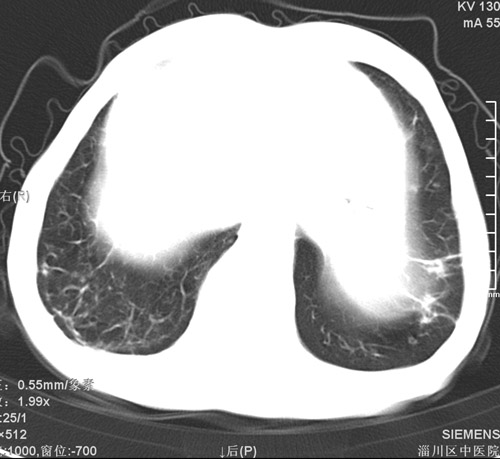

标题: CT17529:男 76 胸背部不适半月 胸透支气管炎 行CT检查 [打印本页]

标题: CT17529:男 76 胸背部不适半月 胸透支气管炎 行CT检查

意见 老年肺 少许炎症 肺大泡 右肺门略大 但支气管通畅  请各位高手指教如何下意见

间质纤维化伴少许炎症!另:肺大泡形成!

慢支肺气肿,肺动脉高压.